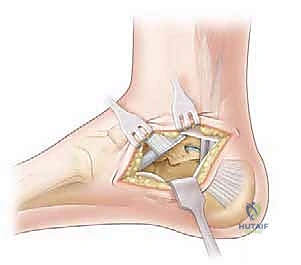

عندما يفشل العلاج التحفظي في توفير راحة دائمة للمريض، وتستمر الآلام في إعاقة حياته اليومية، يصبح التدخل الجراحي هو الخيار الأمثل والضروري. تُعد عملية "إزالة ائتلاف الكاحل العقبي ورأب المفصل بالترقيع" (Excision of Talocalcaneal Coalition with Interposition Arthroplasty) من الجراحات الدقيقة التي تتطلب مهارة عالية، وهي من التخصصات الدقيقة التي يبرع فيها الأستاذ الدكتور محمد هطيف.

الخلاصة الطبية السريعة: يُعد ائتلاف الكاحل العقبي (Talocalcaneal Coalition) اتصالاً أو التحاماً غير طبيعي بين عظمتي الكاحل والعقب في القدم، وهو ما يسبب تشوهاً يتمثل في "القدم المسطحة الصلبة" المصحوبة بألم مزمن وتشنجات عضلية مستمرة. يتضمن العلاج الجراحي المتقدم لهذه الحالة إزالة هذا الائتلاف بدقة متناهية، وإجراء "رأب المفصل بالترقيع" (Interposition Arthroplasty) باستخدام أنسجة دهنية أو عضلية لمنع عودة الالتحام. يهدف هذا التدخل الجراحي إلى استعادة الميكانيكا الحيوية لحركة القدم، تخفيف الألم بشكل جذري، وتحسين جودة حياة المريض. وفي اليمن، يقود الأستاذ الدكتور محمد هطيف، أستاذ جراحة العظام والمفاصل بجامعة صنعاء، ريادة هذا النوع من العمليات الدقيقة والمعقدة بنسب نجاح تضاهي المراكز الطبية العالمية.